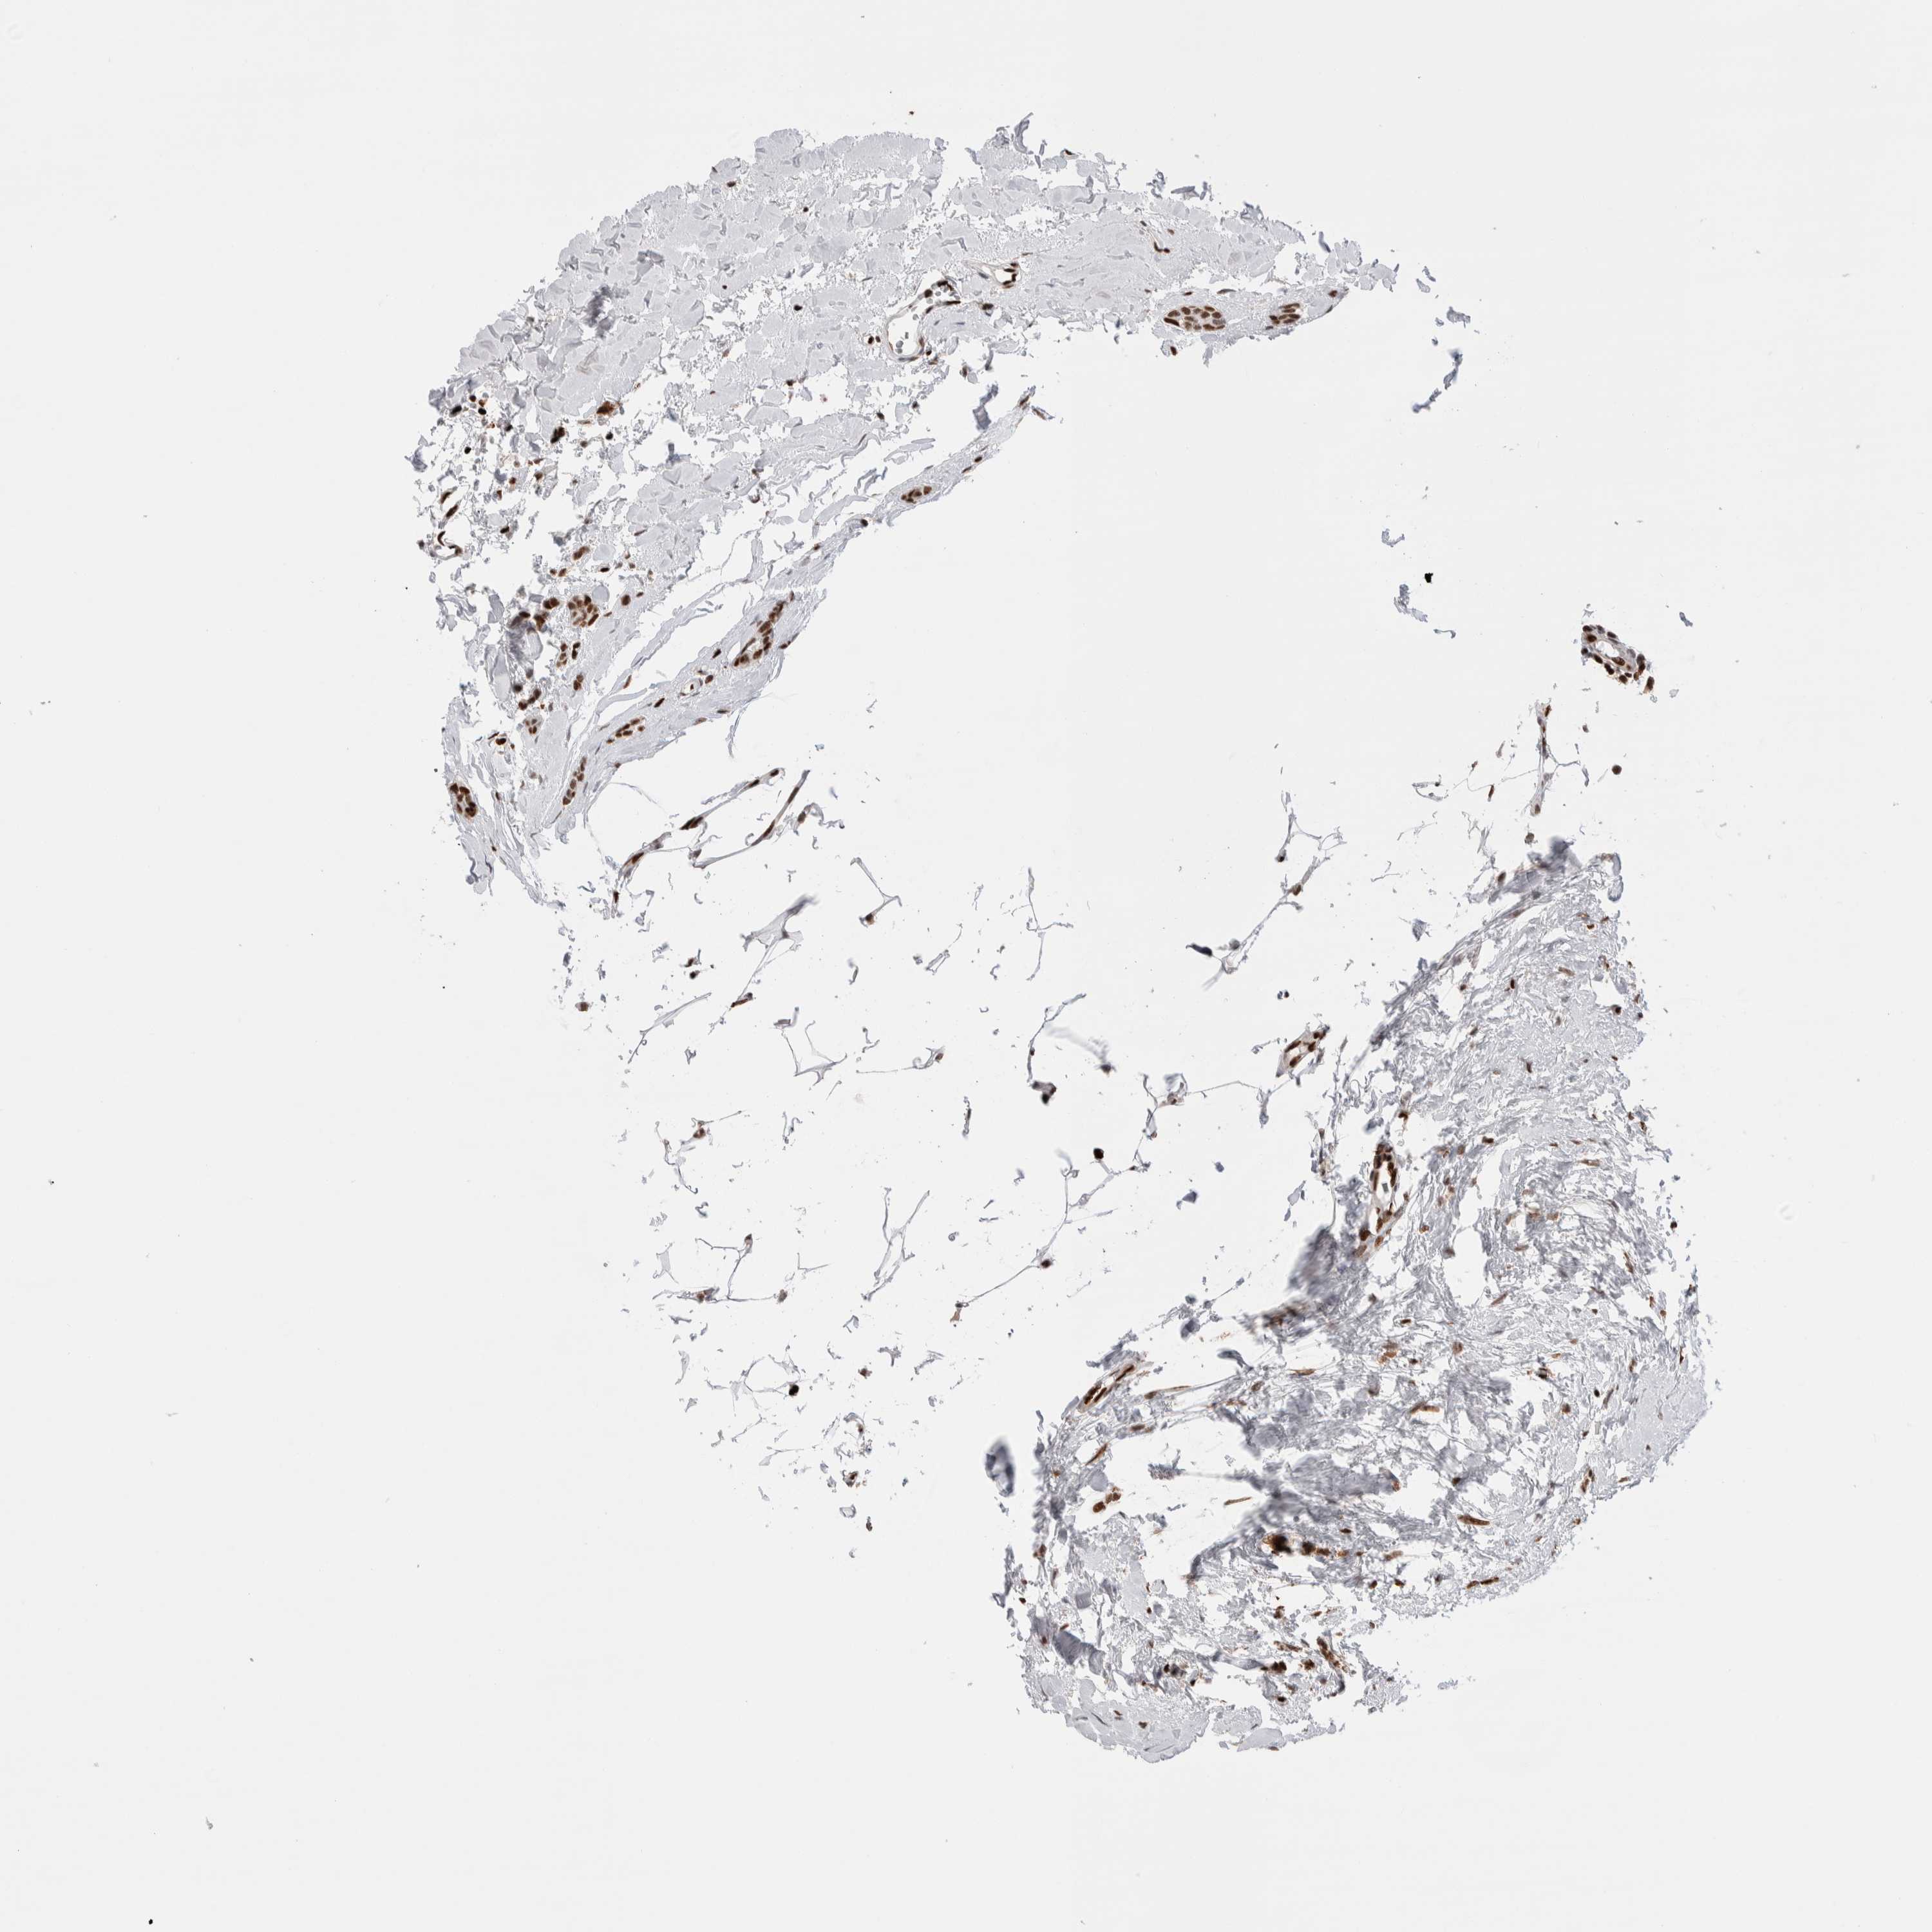

CANCER BREAST CANCER Show tissue menu

BRCA TCGA BRCA VALIDATION PROTEIN EXPRESSION

ANTIBODIES

AND

VALIDATION